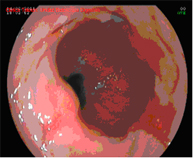

Endoscopic mucosectomy

Endoscopic mucosal resection involves the endoscopic removal of a section of the mucosa and submucosa (in this case of the oesophagus). It is indicated whenever elevated lesions are observed in Barrett's oesophagus during diagnostic endoscopy.

This diagnostic test is conducted on an outpatient basis, with patients remaining under observation in the day hospital for a few hours.